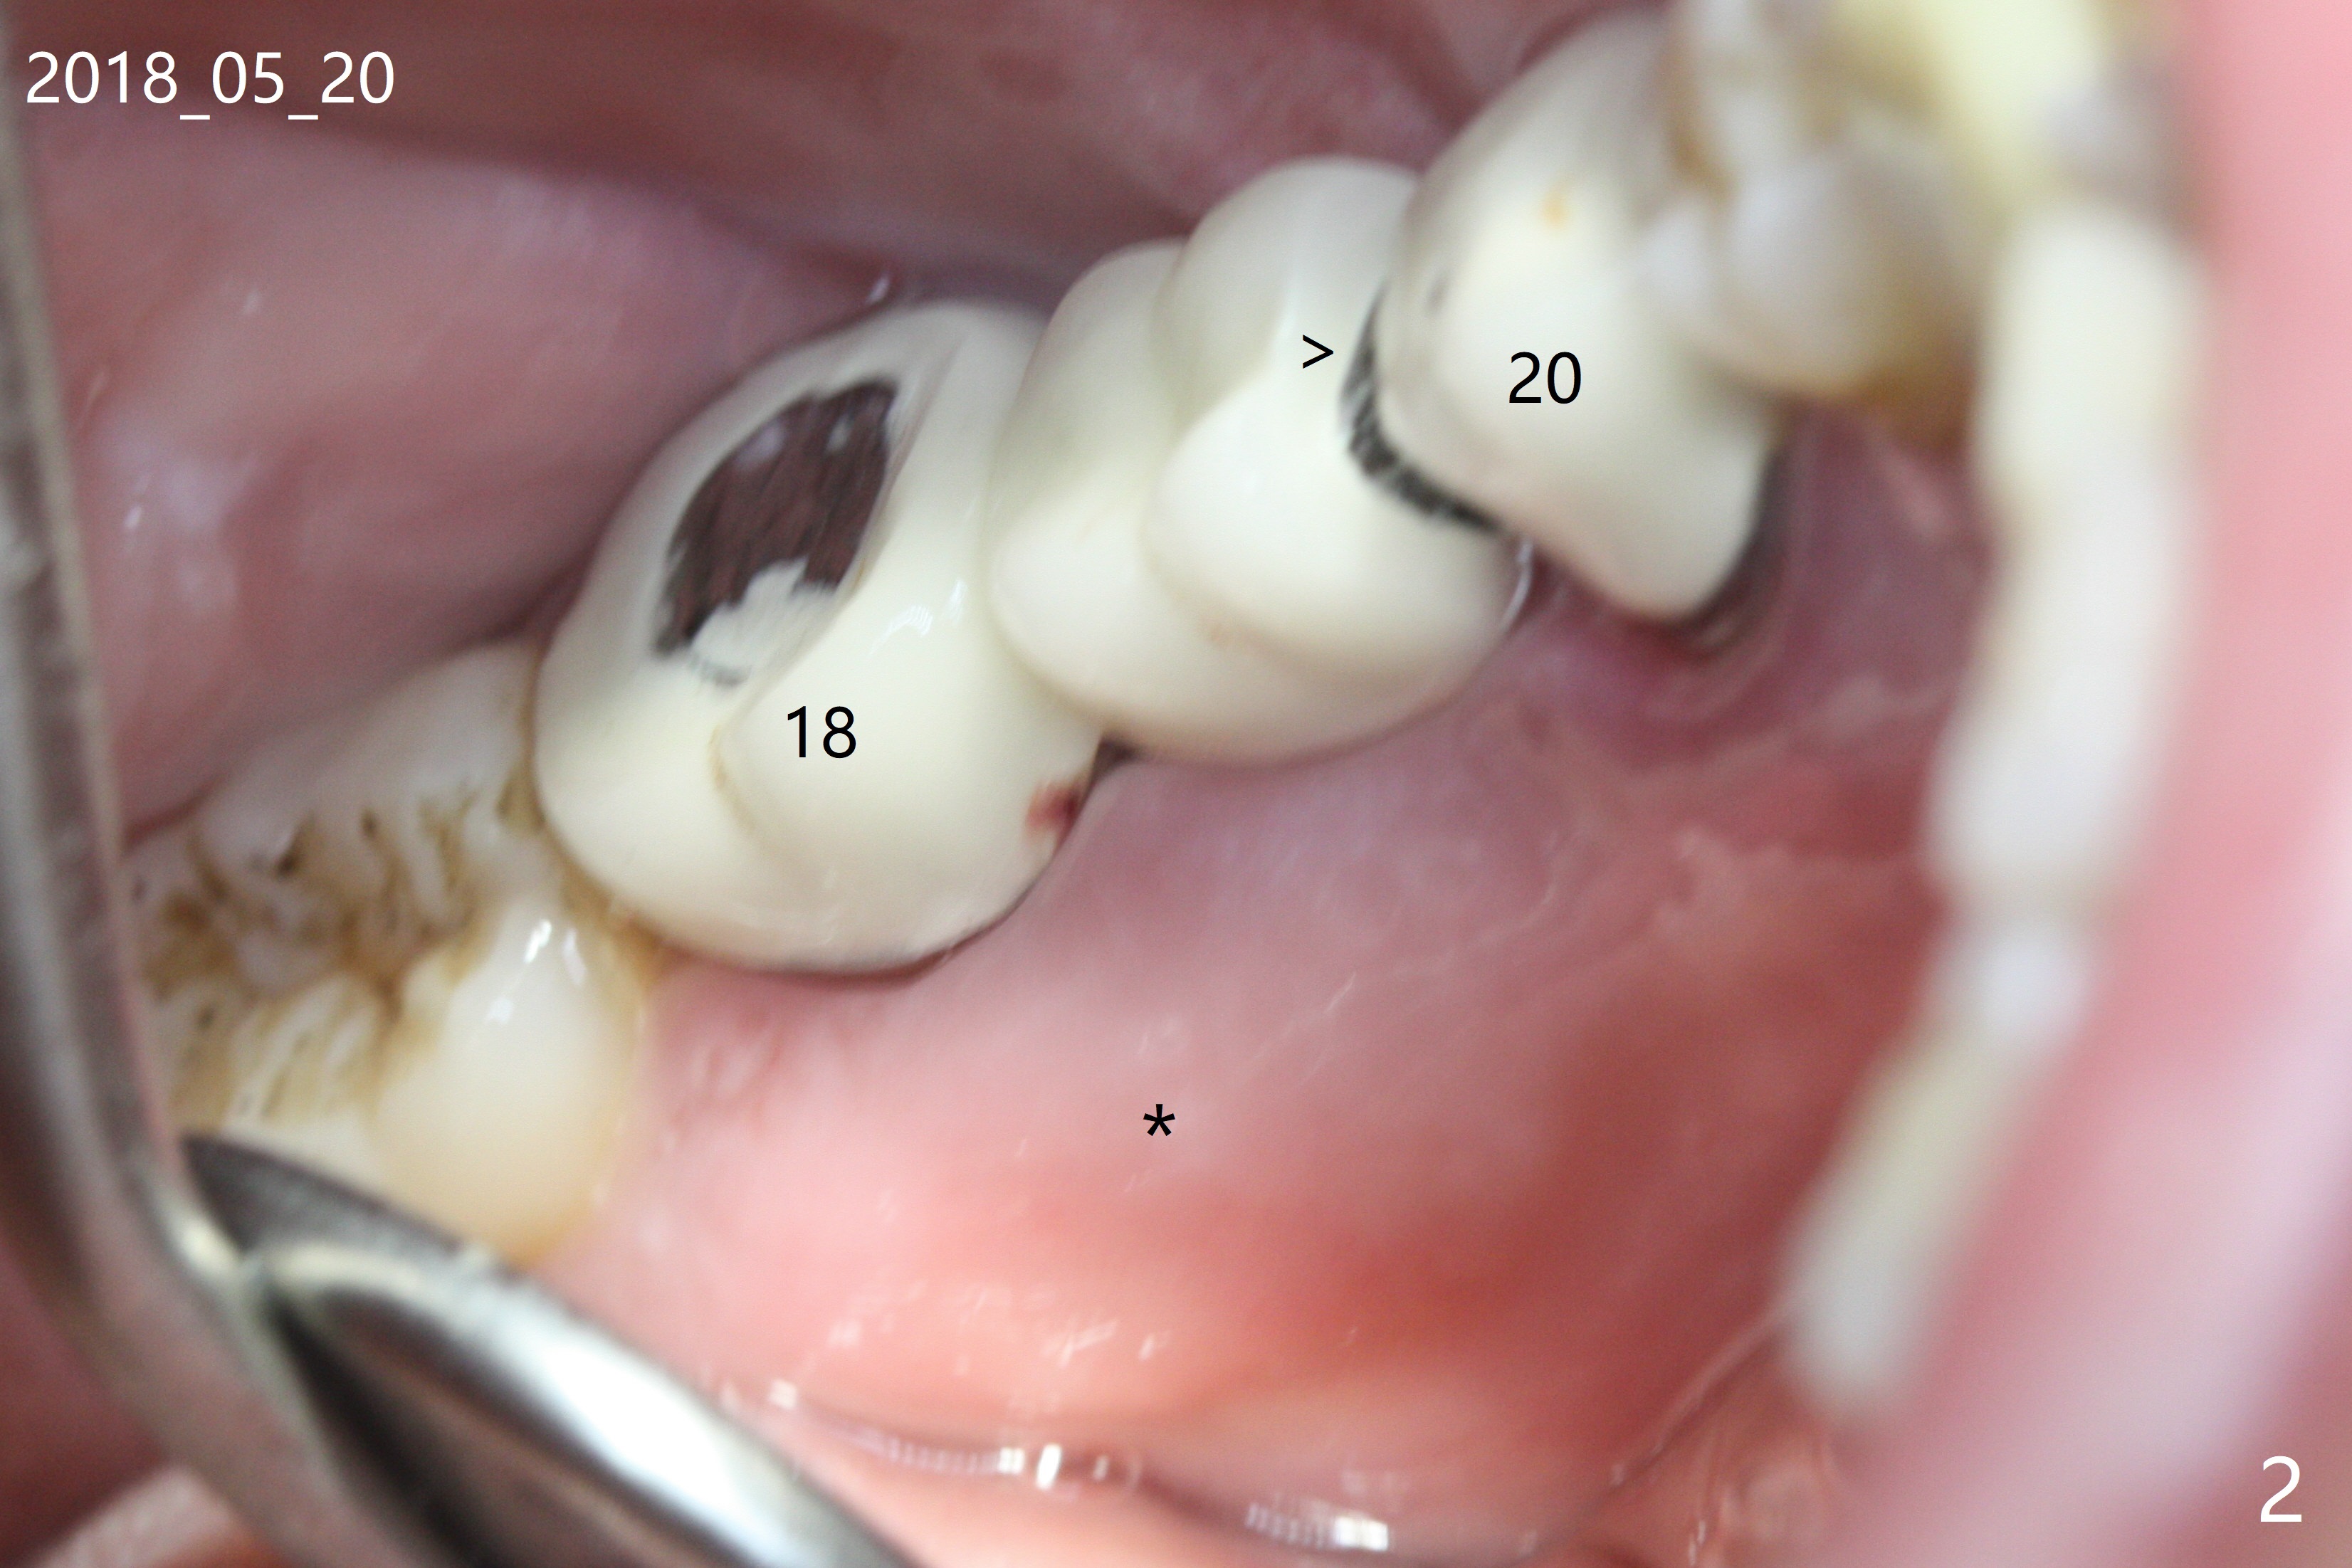

A 46-year-old woman had severe periodontal abscess lingual to #18-20 FPD a year ago (Fig.1,2 *). After SRP and Arestin placement #18 ML, the FPD was sectioned (Fig.2 >) to determine which abutment is to be extracted for implant. Since the sectioning, the patient has been unable to masticate on the left side (Fig.3). With removal of the FPD, CT is taken for surgical guide. Are the abutments salvageable (Fig.4,6)?